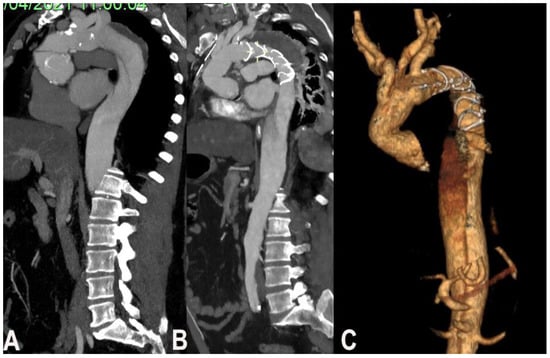

In case of complex thoracic aorta aneurysm that would require a double step surgery may qualify for FET technique. The second step in most of the cases is imperative and it can be even surgical even endovascular. In case of severe dilatation and tortuosity of thoracoabdominal (not suitable for a second endovascular stage) a classic elephant trunk is preferred to facilitate the second open stage repair (Figure 2).

Figure 2. (A). Degenerative aneurism of the descending thoracic aorta, (B). Post FET CT scan.